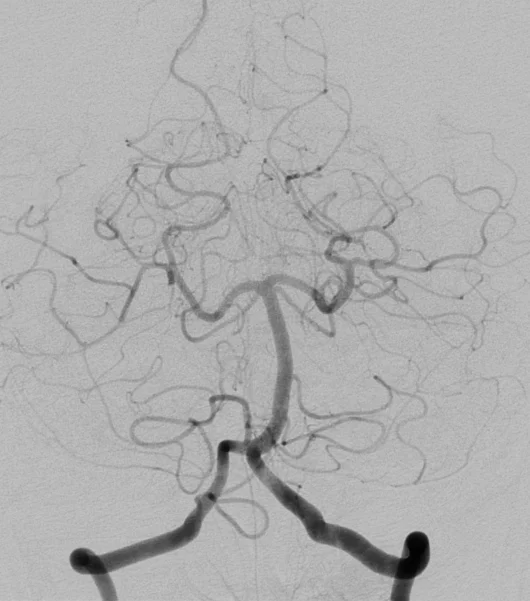

Cet examen invasif, réalisé sous anesthésie locale, permet d’obtenir une analyse morphologique et dynamique très précise des artères et des veines du cerveau ou de la moelle épinière en rendant les vaisseaux sanguins visibles aux rayons X en y injectant un produit de contraste à l’aide d’un tuyau (cathéter) que l’on navigue sous contrôle radiologique depuis le poignet ou le pli inguinal.

L’angiographie cérébrale est un examen diagnostic qui permet de visualiser les vaisseaux qui amènent le sang au cerveau (artères) et ceux qui le ramènent vers le coeur (veines). Les termes artériographie et phlébographie désignent respectivement l’étude spécifique des artères et des veines. Lorsque l’on s’intéresse aux vaisseaux de la moëlle épinière, on parle d’angiographie médullaire.

L’objectif est de rechercher une anomalie des vaisseaux pouvant expliquer vos symptômes. comme une malformation des vaisseaux (anévrysme, malformation artério-veineuse, fistule…), un rétrécissement ou l’occlusion totale d’une artère.

Afin d’éviter les infections, le médecin qui pratique l’examen porte une tenue “stérile”. L’équipe paramédicale désinfecte la peau à hauteur du pli de l’aine et/ou du poignet (le plus souvent à droite). On vous recouvre ensuite d’un champ stérile avec un ou des orifices permettant de travailler. Une anesthésie locale est pratiquée en regard de l’artère fémorale ou radiale et un petit tuyau (introducteur) y est placé. Cet accès permet ensuite de coulisser un second tuyau (cathéter) qui sera guidé par le médecin sous contrôle radiologique jusqu’aux artères que l’on souhaite étudier. Plusieurs séries d’images sont alors réalisées en injectant du produit de contraste iodé dans le flux sanguin à l’aide du cathéter et en faisant des radiographies dynamiques de de ce “moulage” des vaisseaux. A chaque injection, vous pouvez ressentir une sensation de chaleur dans la tête, une sensation de vertige, un goût métallique, des scintillements visuels. Ces symptômes durent quelques secondes et disparaissent ensuite complètement.